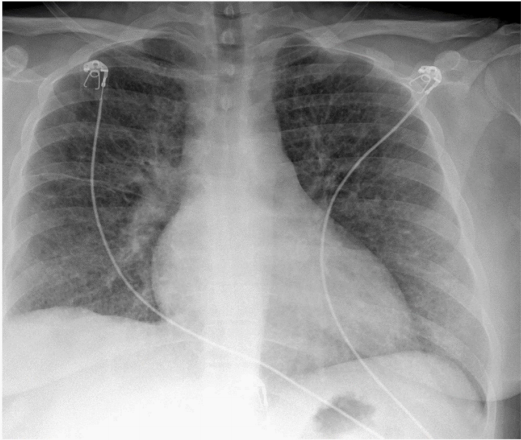

图4 胸膜固定术和拔管后四天的胸片提示右侧气胸消退

患者最终诊断为淋巴管平滑肌瘤病(lymphangioleiomyomatosis,LAM)。行胸廓造口术治疗气胸,随后对继发性自发性气胸行聚维酮碘

胸膜固定术(图4)。患者出院时成功拔除胸管,转至LAM中心接受进一步治疗。